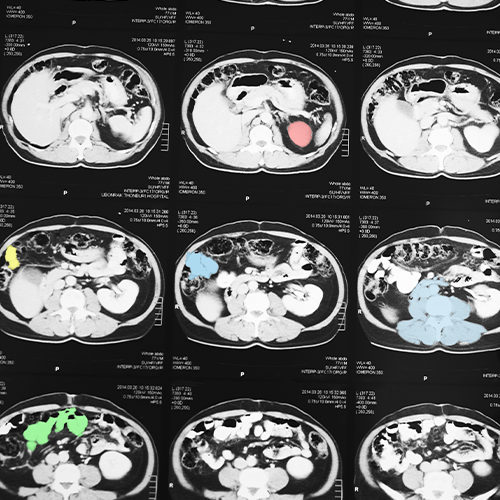

Organ & Tissue Segmentation

We annotate organs and tissues across modalities, enabling AI to differentiate structures for diagnosis and treatment planning.

Tumor & Lesion Annotation

Detailed labeling of tumors, nodules, and lesions helps AI models detect cancers and other abnormalities at early stages.

Multi-Modal Annotation

Cross-referencing X-rays, CTs, MRIs, and pathology slides enables holistic AI models capable of integrating different medical perspectives.